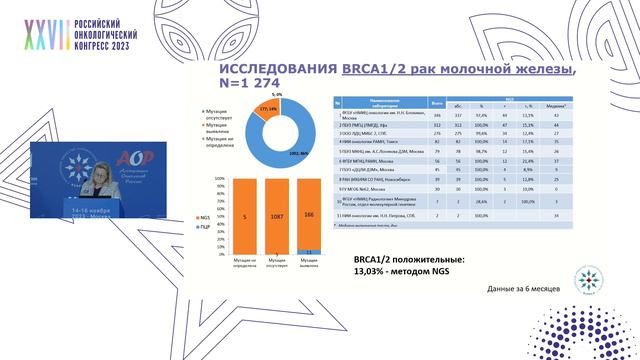

Таргетная терапия РМЖ: Инновации в лечении

Раздел: Кадры-подсказки